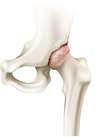

L’arthrose de hanche (aussi appelée coxarthrose) est une affection dégénérative, chronique, qui se manifeste par des douleurs et une diminution de la mobilité de l’articulation potentiellement handicapante. Elle peut évoluer lentement pendant une dizaine d’année ou devenir d’emblée invalidante.

L’arthrose désigne un processus d’usure du cartilage liée au vieillissement. Ce n’est pas une fatalité liée à l’âge. Elle cause des dommages irréversible du cartilage qui perd au fur et à mesure son rôle de surface de glissement et d’amortisseur. La pression sur l’os s’accroît à mesure que l’épaisseur cartilagineuse diminue. Des excroissances osseuses, appelées ostéophytes, des kystes osseux et des ulcérations cartilagineuses se forment progressivement.

En réponse, la membrane synoviale devient inflammatoire et produit un liquide synovial. L’excès de pression articulaire et l’inflammation sont les causent des douleurs de hanche. La perte de congruence de l’articulation entraîne quant à elle, une diminution de la mobilité articulaire.